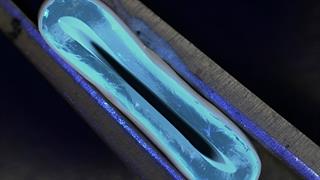

Τεχνητά αιμοφόρα αγγεία θα μπορούσαν να βελτιώνουν το αποτέλεσμα του bypass